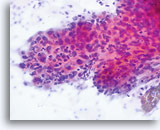

No diagnostic classification causes more debate than Atypical Squamous Cells (ASC). New terms rose from the revised classification of The Bethesda System (TBS) in 2001 and remain for TBS 2014. TBS indicates that the ASC category should be the diagnostic consideration when squamous abnormalities are present that are more marked than those attributable to reactive changes, but fall qualitatively or quantitatively short of the diagnostic criteria for a low grade or high grade squamous intraepithelial lesion. Furthermore, TBS stresses the importance of qualifying this diagnosis as “undetermined significance” (ASC-US) or “cannot exclude HSIL.” (ASC-H)

The proper classification of ASC challenges the cytotechnologist and pathologist and, writing any chapter describing the morphologic criteria of ASC is challenging, given the subjectivity of this interpretation. Since the adoption of TBS, laboratory professionals interpreting the conventional Pap smear may have used this category as a “catch all” for smears that are difficult to classify.

Artifacts inherent to the conventional Pap smear, such as air-dried or partially obscured cells, may result in an ASC diagnosis. The degree of apparent atypia in reactive cells may also be exaggerated by air-drying or smearing. These issues result in the artifacts that make it difficult for the cytotechnologist and pathologist to adequately visualize the nuclear detail of the cells in question, resulting in a less than definitive diagnosis.

The immediate wet fixation that is used in the ThinPrep process may allow the pathologist and cytotechnologist to move away from the ASC “catch all” and better differentiate between cellular changes due to reactive conditions, definitive squamous atypia, and dysplastic lesions. This is not to say that ASC interpretations are eliminated by the adoption of the ThinPrep Pap Test, but the laboratory staff has the opportunity to refine their morphologic criteria, eliminating certain “ASC” cases arising from poor preparation, and better identifying cases that may

harbor abnormality.

The ThinPrep Pap Test® minimizes the troublesome artifacts inherent in smear and spray fixation. This allows for

the nucleus to be adequately visualized facilitating a more definitive diagnosis. The epithelial cells that are generally incorporated in the ASC category are the mature squamous and squamous metaplastic cells exhibiting changes that are minimal and fall short of a diagnosis of LSIL or HSIL. The nuclei are slightly enlarged and this enlargement is compared to the normal entity of the same cell type. The nuclei may show slight nuclear membrane irregularities but are more often smooth. When dealing with the metaplastic component, one needs to make sure that the irregularities aren’t due to a vacuole(s) pushing the nucleus into the aberrant shape. The chromatin pattern is finely granular and evenly distributed. Chromocenters or nucleoli are generally inconspicuous or absent unless a reactive process is occurring in conjunction with the atypia at which point the differential diagnosis of reactive needs to be considered depending upon the presence or lack of the other criteria.

With either conventional or ThinPrep® slides, an ASC interpretation may arise from any of several different cellular changes, including but not limited to, squamous atypia, atypical squamous metaplasia, and atypical parakeratosis. The criteria for ASC on the ThinPrep Pap Test are as follows:

The images that follow are ThinPrep® Pap Test specimens that reasonably could be interpreted as reactive changes,

ASC-US, and LSIL.

As previously mentioned, ASC will not be eliminated by the adoption of the ThinPrep® Pap Test. In fact, the better cellular preservation that is afforded by liquid fixation can lead to over interpretation of nuclear size and chromatin as ASC if one is not familiar with the consequences of liquid fixation as discussed in the introductory material regarding “microscopic evaluation of ThinPrep slides”. There are circumstances where laboratory staff may transiently experience an increase in their use of ASC classification immediately after adoption of the ThinPrep Pap Test, then, after gaining experience, see that rate drop below that which was experienced with the conventional Pap.

ASC, as long as it remains a category in TBS, will be used by pathologists because of inherent subjectivity of human diagnosis, and variable interpretation of criteria. Also important is the biologic nature of Human Papilloma Virus (HPV) that causes morphologic perturbations in cells that are less than LSIL. The morphologic changes caused by HPV are discussed in greater detail in the section covering Low Grade Squamous Intraepithelial Lesions. The role of this virus in the causation of ASC has created the opportunity to determine the relative risk of ASC changes by the determination of high- vs. low-risk types of virus through ancillary testing of the material in the ThinPrep Pap Test vial.